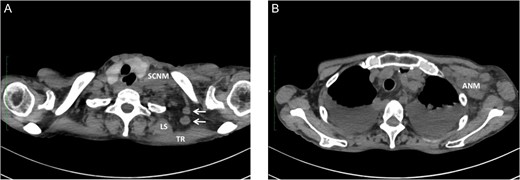

We have had three cases of this unusual LNM from cancer of the thoracic esophagus to date. Clinicopathological characteristics and survival are presented in Table 1. This unusual LNM developed after esophagectomy in two patients (cases 1 and 2, Fig. 2) and was found at presentation in a third patient (case 3, Fig. 3).

Metastasis of the supraclavicular nodes (SCNM), the nodes located between TR and LS (arrow) (A), and the axillary nodes (ANM) (B) developed 4 months after esophagectomy.

Undifferentiated carcinoma was confirmed by excisional biopsy of the tumor located between TR and LS (arrow).

One possible explanation of this phenomenon is retrograde spread from SCNM. Komatsu et al. [3] reported four cases of axillary node metastasis (ANM) of squamous cell carcinoma of the upper- and mid-thoracic esophagus. All ANM developed on the left side, with the preceding or simultaneous left SCNM. The supraclavicular nodes are well known as regional lymph nodes in breast cancer, and lymphatics from the axillary nodes are considered to communicate with the supraclavicular nodes. Based on experimental and clinical observations, they concluded that ANM might be caused by retrograde flow owing to lymphatic blockade by SCNM in esophageal cancer [3, 4]. A similar mechanism was speculated in our cases 1 and 2, in which preceding or simultaneous ipsilateral SCNM also developed. Interestingly, simultaneous ANM was also seen in case 2.